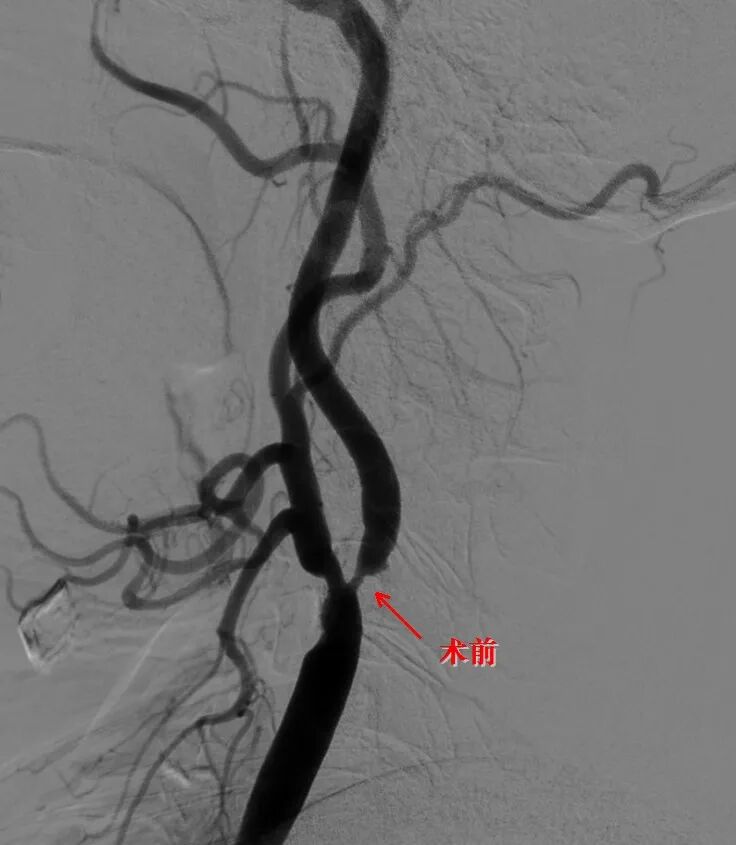

患者李奶奶,77岁,因反复头晕、左上肢麻木来院就诊。脑血管造影结果显示:右侧颈内动脉重度狭窄 + 同侧颈内动脉颅内段2个动脉瘤。

狭窄可致脑梗,动脉瘤可致脑出血——两大隐患同时存在,手术难度倍增!

• 神经内科率先出手:吴秋义主任医师、徐瑶嘉医师携手微创介入,在狭窄部位精准植入支架,撑开血管,恢复脑部正常血流。